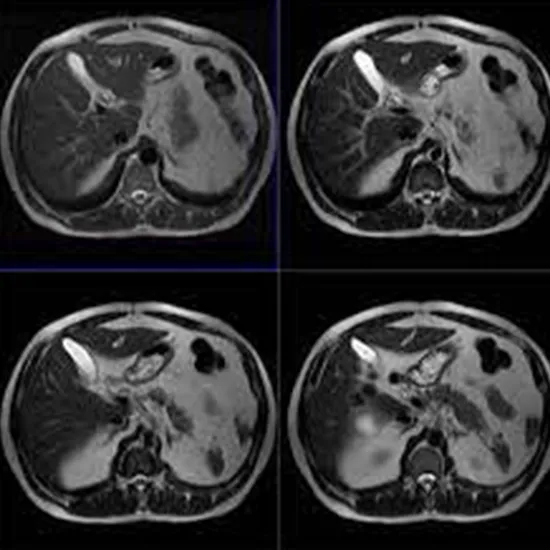

MRI Upper Abdomen and MRCP

A magnetic resonance cholangiopancreatography is a comprehensive form of MRI examination. It is used by your doctor to examine the biliary and pancreatic systems.

MRI and MRCP imaging are popular diagnostic techniques for bile duct malignancy (cholangiocarcinoma). It can reveal a bile duct tumor as well as other issues such as infection or irritation.